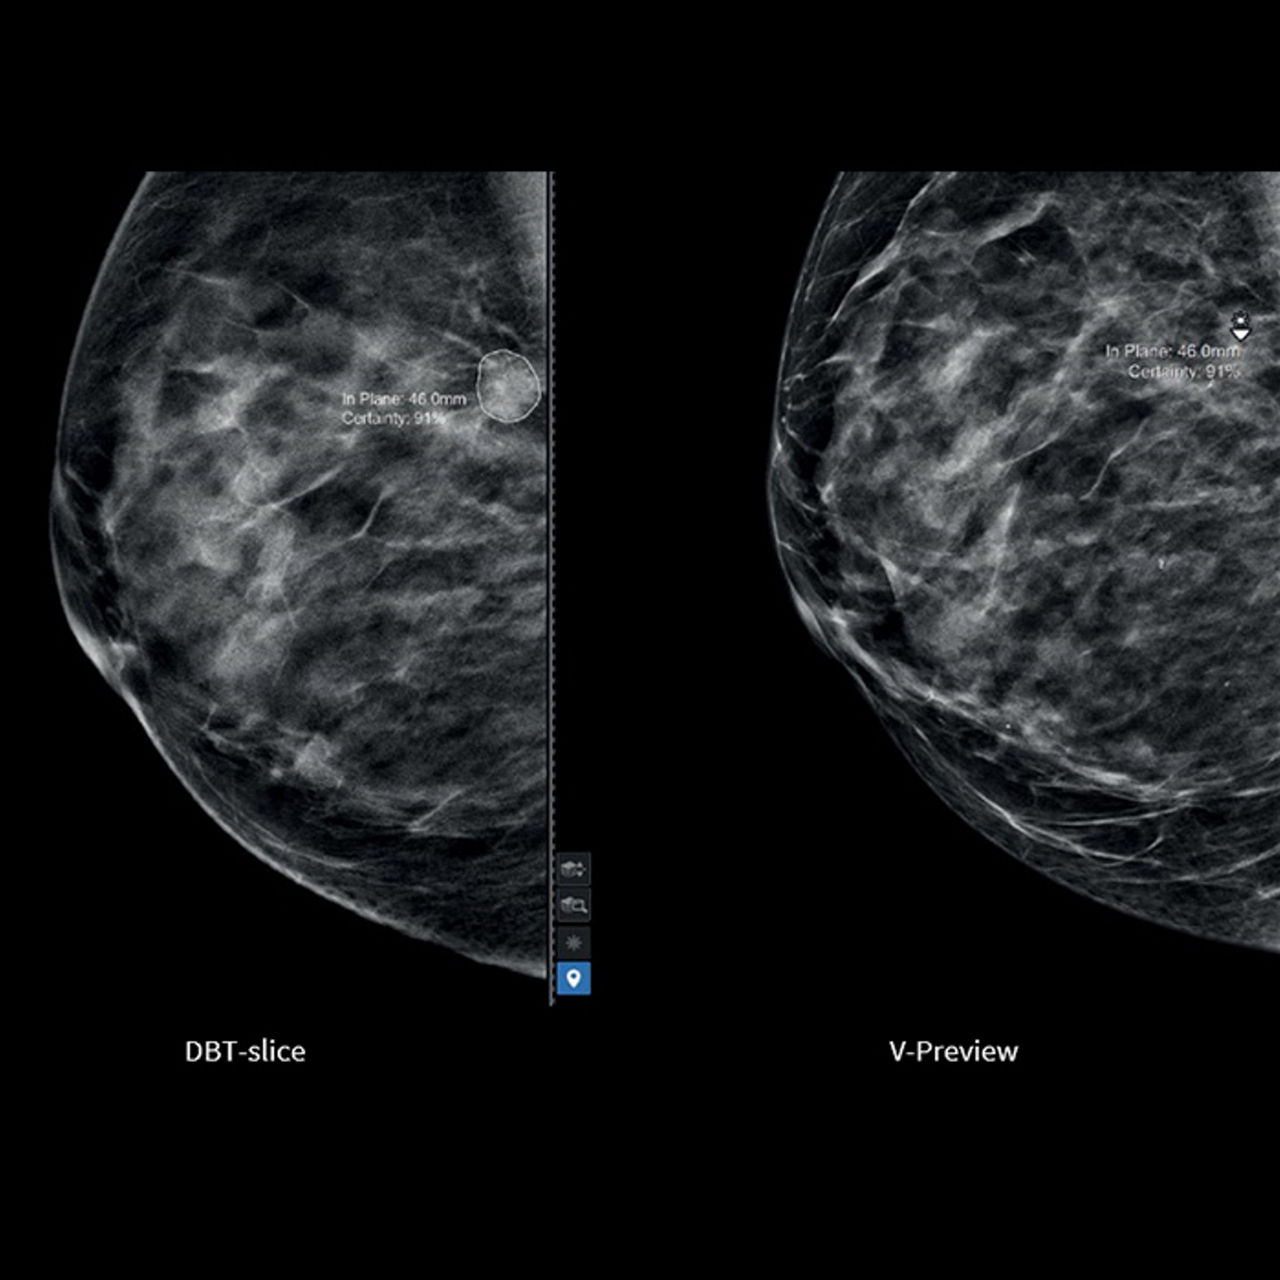

ProFound AI® for DBT

Trained with one of the largest available 3D image datasets, ProFound AI provides radiologists with crucial information, such as lesion Certainty of Finding and Case Scores, which assists in prioritizing caseload, clinical decision-making and may help to reduce physician burnout3.

Easy navigation between the V-Preview and the slices containing the AI markers.